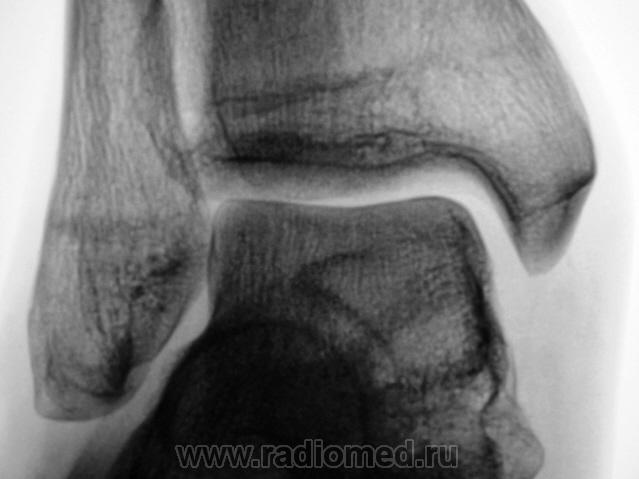

Пол пациента: Мужской пол Тип патологии: Другое Область исследования: Скелетно-мышечная система Методы исследования: Rg Пациент направлен врачом хирургом в рентгеновский кабинет по поводу болей в голеностопном суставе. Произведена рентгенография голеностопного сустава Ваше мнение уважаемые коллеги? Tue, 06/10/2009 - 22:21 #1 Ермолаев Offline Last seen: 8 years 11 months ago Joined: 07.02.2009 - 16:33 Posts: 670 Думаю, что имеет место артроз голеностопного сустава и таранно-ладьевидного, таранно-пяточного суставов. Только это следствие, а причина мне видится в наличии повреждения дистального межберцового синдесмоза. dok Tue, 06/10/2009 - 22:48 #2 В.Б. Серов Offline Last seen: 1 month 2 weeks ago Joined: 16.07.2008 - 10:15 Posts: 1361 Дугообразная деформация костей, с линейными зонами перестройки, плоскостопие. Полный комплект дефектов Зри в корень!

Думаю, что имеет место артроз голеностопного сустава и таранно-ладьевидного, таранно-пяточного суставов. Только это следствие, а причина мне видится в наличии повреждения дистального межберцового синдесмоза.

Дугообразная деформация костей, с линейными зонами перестройки, плоскостопие. Полный комплект дефектов